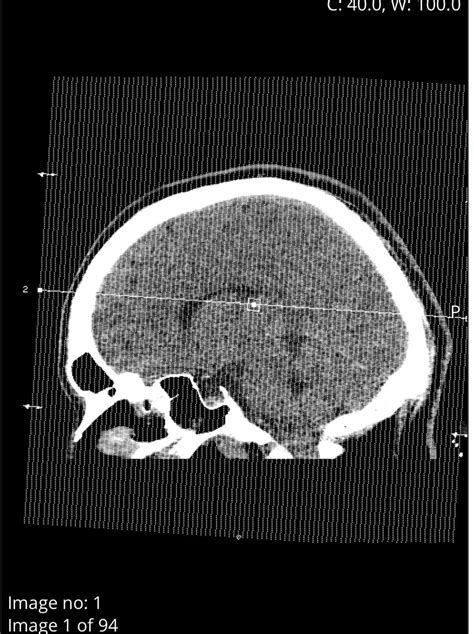

Diagnosing a cyst in brain typically involves a combination of medical history, physical examination, and imaging tests. The most common diagnostic tools include:

• Magnetic Resonance Imaging (MRI)

• Computed Tomography (CT) scan

MRI is often the preferred method for diagnosing brain cysts because it provides detailed images of the brain and can help differentiate between different types of cysts. CT scans are also useful and can be particularly helpful in emergency situations where quick imaging is needed.